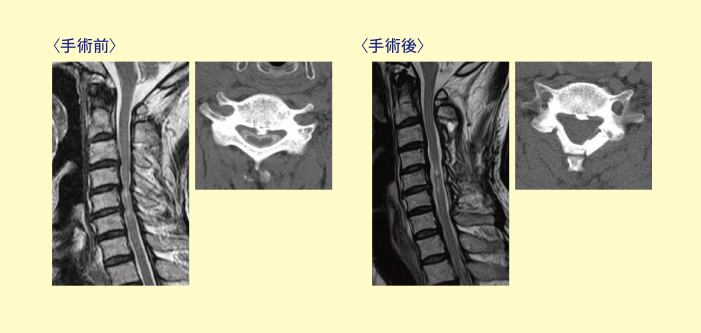

頚椎椎弓形成術(けいついついきゅうけいせいじゅつ) 片開き式 とは

頚部もしくは胸部の後方に約3cmの皮膚切開を行い、手術用の顕微鏡をみながら、頚椎椎弓(頚椎の後ろの屋根)片開き式に拡大し、人工の骨を用いて脊髄を除圧する方法です。手術時間は1~2時間程度で、麻酔時間を合わせて、手術場には3~4時間ほど入っています。この手術での出血は100cc以下で、高度な貧血がない限り輸血を行うことはありません。